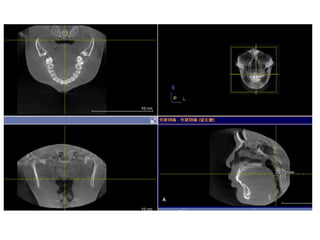

In a healthy sleeping child, the mouth is

typically closed, the oral cavity is

collapsed, and the nasopharynx and

hypopharynx are patent with minimal

wall motion